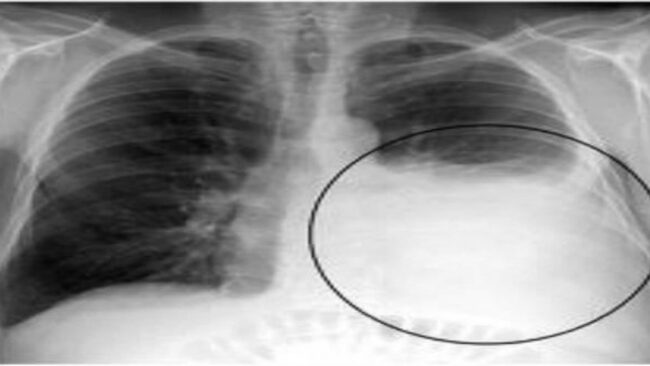

- Chụp X-quang lồng ngực: biện pháp cận lâm sàng này giúp phát hiện tràn dịch màng phổi khu trú, rãnh liên thùy, khối u ở mô phổi, …

- Chụp CT-Scan ngực: Chụp CT có độ chính xác cao, do đó có thể phát hiện ra nguyên nhân gây nên tràn dịch màng phổi ác tính do u phổi và bản chất của khối u, cho chúng ta thấy được nhu mô phổi đã bị che lấp do dịch màng phổi tràn nhiều.